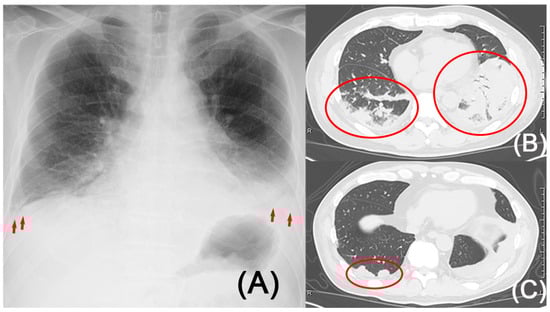

2. Case Presentation